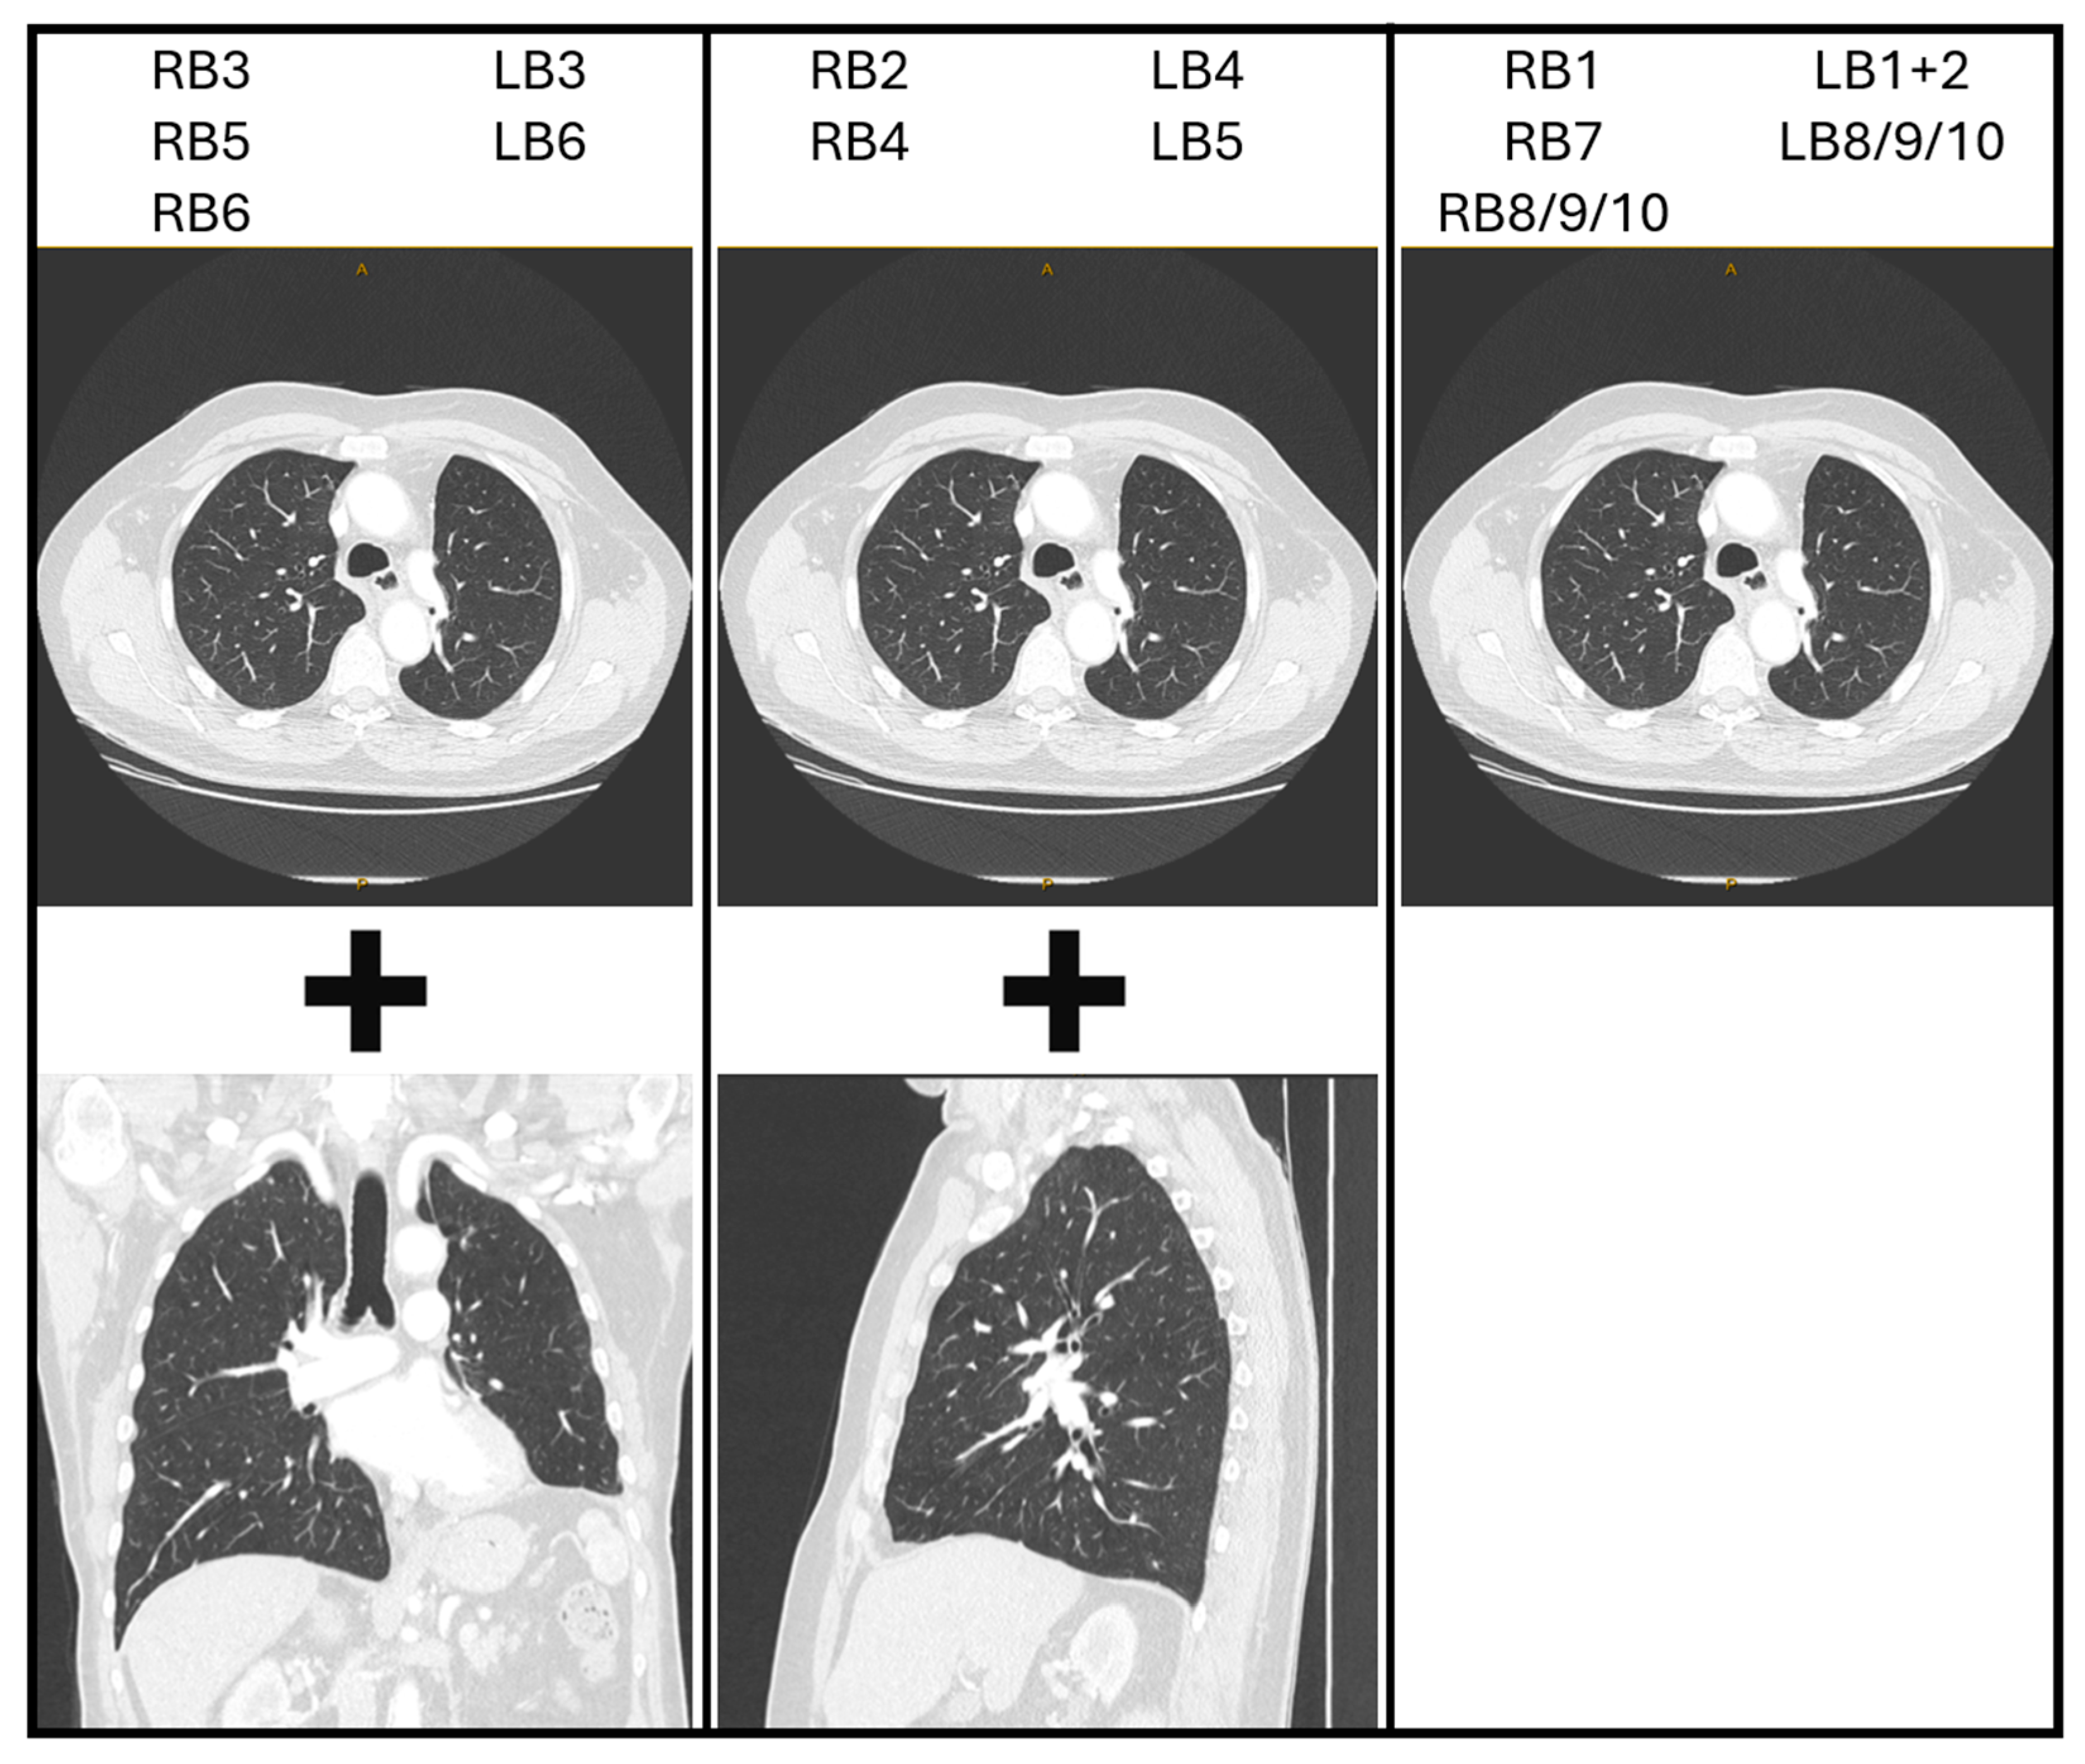

Step 2. Transform the CT image—optional (Figure 1D)

Transformation (flipping and/or rotation) of the CT image is not essential, provided the bronchoscopist can maintain a spatial awareness of the anatomical directions as they draw the map. These anatomical directions are often marked on the edges of the CT images as well. Each bronchoscopist can therefore decide if they prefer to perform such transformations on the CT image or in their mind. However, it may be more instinctive if axial images are transformed in a manner that assists the bronchoscopist in imagining themselves navigating the CT images as if they were performing the bronchoscopy. Therefore, the authors suggest initially flipping the image horizontally to reflect the anatomical orientation as the bronchoscope enters the trachea, then rotating 90 degrees clockwise or counterclockwise for left and right-sided lesions, respectively. This reflects the rotation of the bronchoscope as occurs when the left or right main bronchus is intubated. Subsequent transformations may be natural for some users, such as flipping the CT image vertically for upper lobe lesions in the apical segments. It may also be helpful to use sagittal reconstructions for laterally projecting segmental airways and coronal reconstructions for anteriorly/posteriorly projecting segmental airways. Because the ostium of a segmental airway is rarely facing in a precise anatomical direction, consider either using the closest direction or a combination of axial and reconstructed CT images side-by-side. Potential combinations are suggested in

Figure 2, although considering the individual anatomy on a case-by-case basis is most reliable.

Figure 2.

Potential CT image reconstructions for each segmental bronchus. RB = right segmental bronchi. LB = left segmental bronchi. For example, if navigating via the RB3 segmental airway, consider using axial images (with a horizontal flip ± 90-degree counterclockwise rotation) and coronal reconstructions.

Figure 2.

Potential CT image reconstructions for each segmental bronchus. RB = right segmental bronchi. LB = left segmental bronchi. For example, if navigating via the RB3 segmental airway, consider using axial images (with a horizontal flip ± 90-degree counterclockwise rotation) and coronal reconstructions.